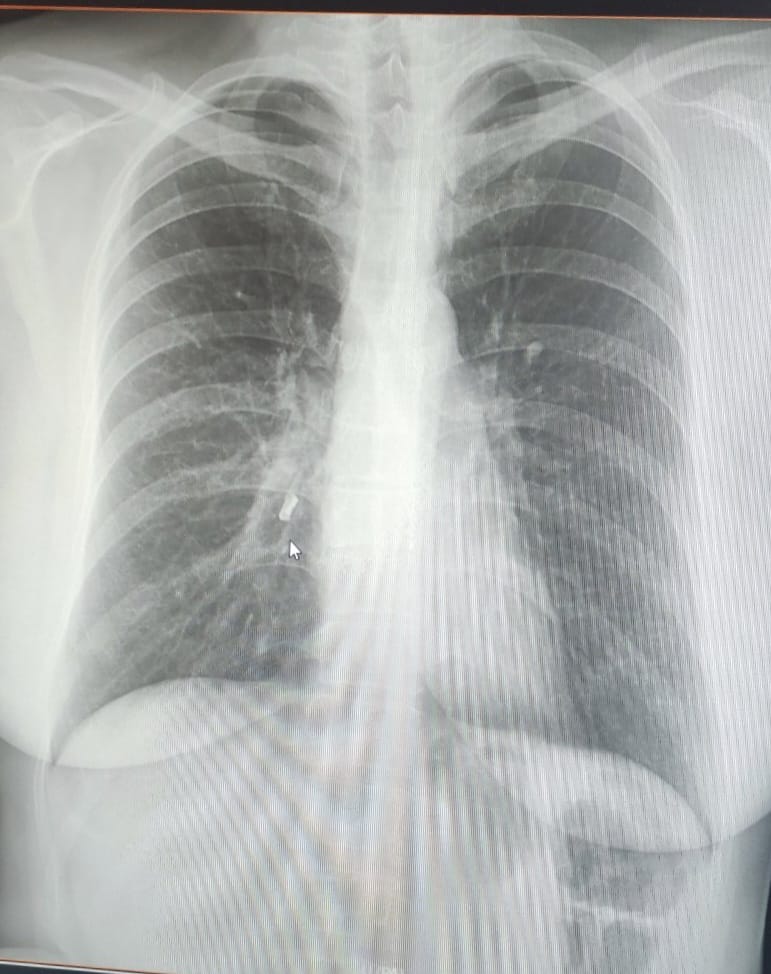

У Центрі легеневого здоров'я жінку оглянув лікар-пульмонолог та відправив її на додаткові обстеження. Рентген із контрастом показав, що в одному з бронхів знаходиться зуб.

Фото: facebook.com/cph.lviv